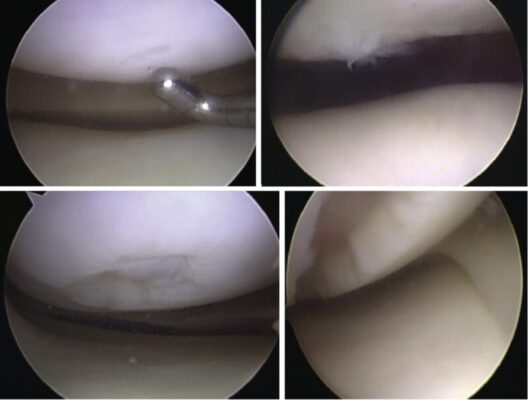

Outerbridge đã phân loại các tổn thương sụn vào năm 1961 và đây vẫn là phân loại hiện tại được sử dụng cho đến nay (Hình 1).

- độ I (phía trên bên trái): sụn mềm và sưng;

- độ II (phía trên bên phải): khiếm khuyết một phần độ dày với các khe nứt trên bề mặt không chạm đến xương dưới sụn hoặc vượt quá 1,5 cm đường kính;

- độ III (phía dưới bên trái): nứt đến mức xương dưới sụn ở một vùng có đường kính lớn hơn 1,5 cm;

- độ IV (dưới cùng bên phải): lộ xương dưới sụn.